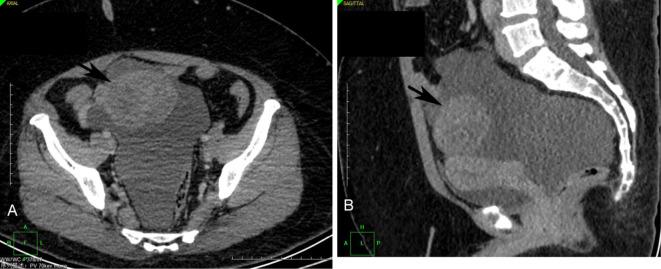

Ovary microcystic stromal tumor (MCST) is an extremely rare subtype of sex cord-stromal neoplasm, and only 57 cases have been reported. We herein report a unique case of ovarian MCST with positive nestin expression in a 39-year-old Chinese woman. The tumor showed microcystic stromal histological structures and characteristically expressed the CD10, WT-1, and Ki67 proteins. A molecular analysis identified a point mutation (c.110C > T) in exon 3 of the CTNNB1 gene. To our knowledge, no report has described a case of ovarian MCST with positive staining for nestin protein. Our study provides new insights into the tumor biology of ovarian MCST.

卵巢微囊型基质瘤(MCST)是一种极为罕见的性索-间质肿瘤亚型,仅有 57 例报道。本文报道了一例独特的卵巢 MCST 病例,患者为 39 岁中国女性,巢蛋白呈阳性表达。肿瘤呈微囊型基质组织学结构,特征性表达 CD10、WT-1 和 Ki67 蛋白。分子分析发现 CTNNB1 基因外显子 3 存在点突变(c.110C > T)。据我们所知,尚无巢蛋白阳性染色的卵巢 MCST 病例报道。本研究为卵巢 MCST 的肿瘤生物学提供了新的见解。